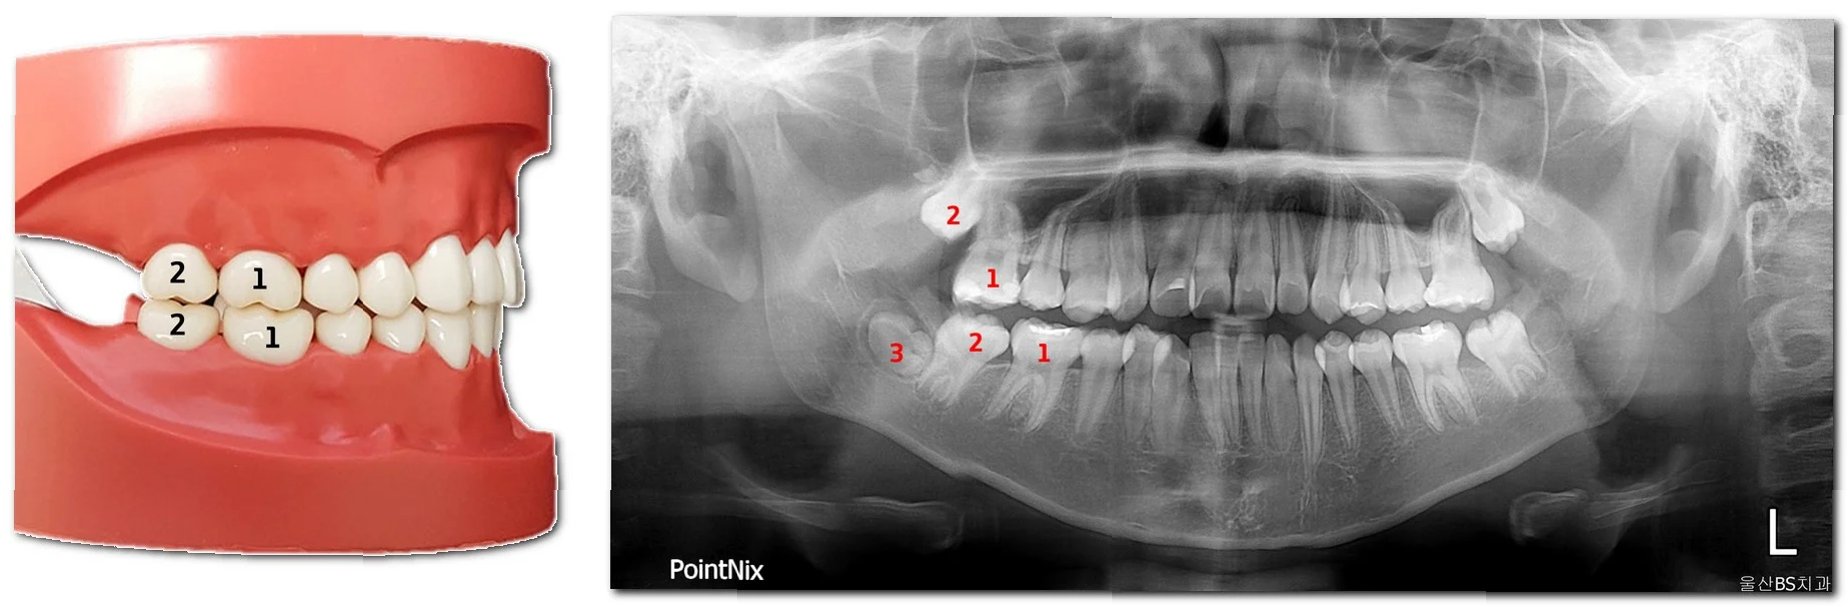

이소 맹출은 치아가 정상적인 위치에서 벗어나 다른 부위에 맹출하는 현상을 의미합니다. 이는 다양한 원인에 의해 발생할 수 있으며, 덧니, 매복치, 유치 잔존 등의 형태로 나타날 수 있습니다. 이소 맹출은 심미적인 문제뿐만 아니라, 잇몸 염증, 충치 발생 위험 증가, 턱관절 장애 등을 유발할 수 있으므로, 조기에 발견하여 적절한 치료를 받는 것이 중요합니다. 특히, 영구치가 맹출하는 과정에서 이소 맹출이 발생할 경우, 치아 배열에 심각한 영향을 미칠 수 있으므로 주의 깊게 관찰해야 합니다.

치아 맹출 지연과 이소 맹출의 치료 방법은 원인과 증상에 따라 다릅니다. 맹출 지연의 경우, 단순한 맹출 지연이라면 경과를 관찰하며 기다릴 수 있습니다. 하지만, 다른 문제가 동반된다면, 엑스레이 촬영을 통해 치아의 발육 상태를 확인하고, 맹출을 방해하는 요인(과잉치, 낭종 등)을 제거하는 치료를 진행할 수 있습니다. 이소 맹출의 경우, 치아의 위치를 바로잡기 위해 교정 치료가 필요할 수 있습니다. 덧니의 경우, 공간이 부족하다면 발치를 통해 공간을 확보하고 교정 치료를 진행할 수 있으며, 매복치의 경우, 맹출 유도술을 통해 치아를 제 위치로 나오게 할 수 있습니다. 치료 시기는 치아의 성장 상태와 환자의 상황에 따라 달라지므로, 치과 전문의와 충분히 상담하여 적절한 치료 계획을 세우는 것이 중요합니다.